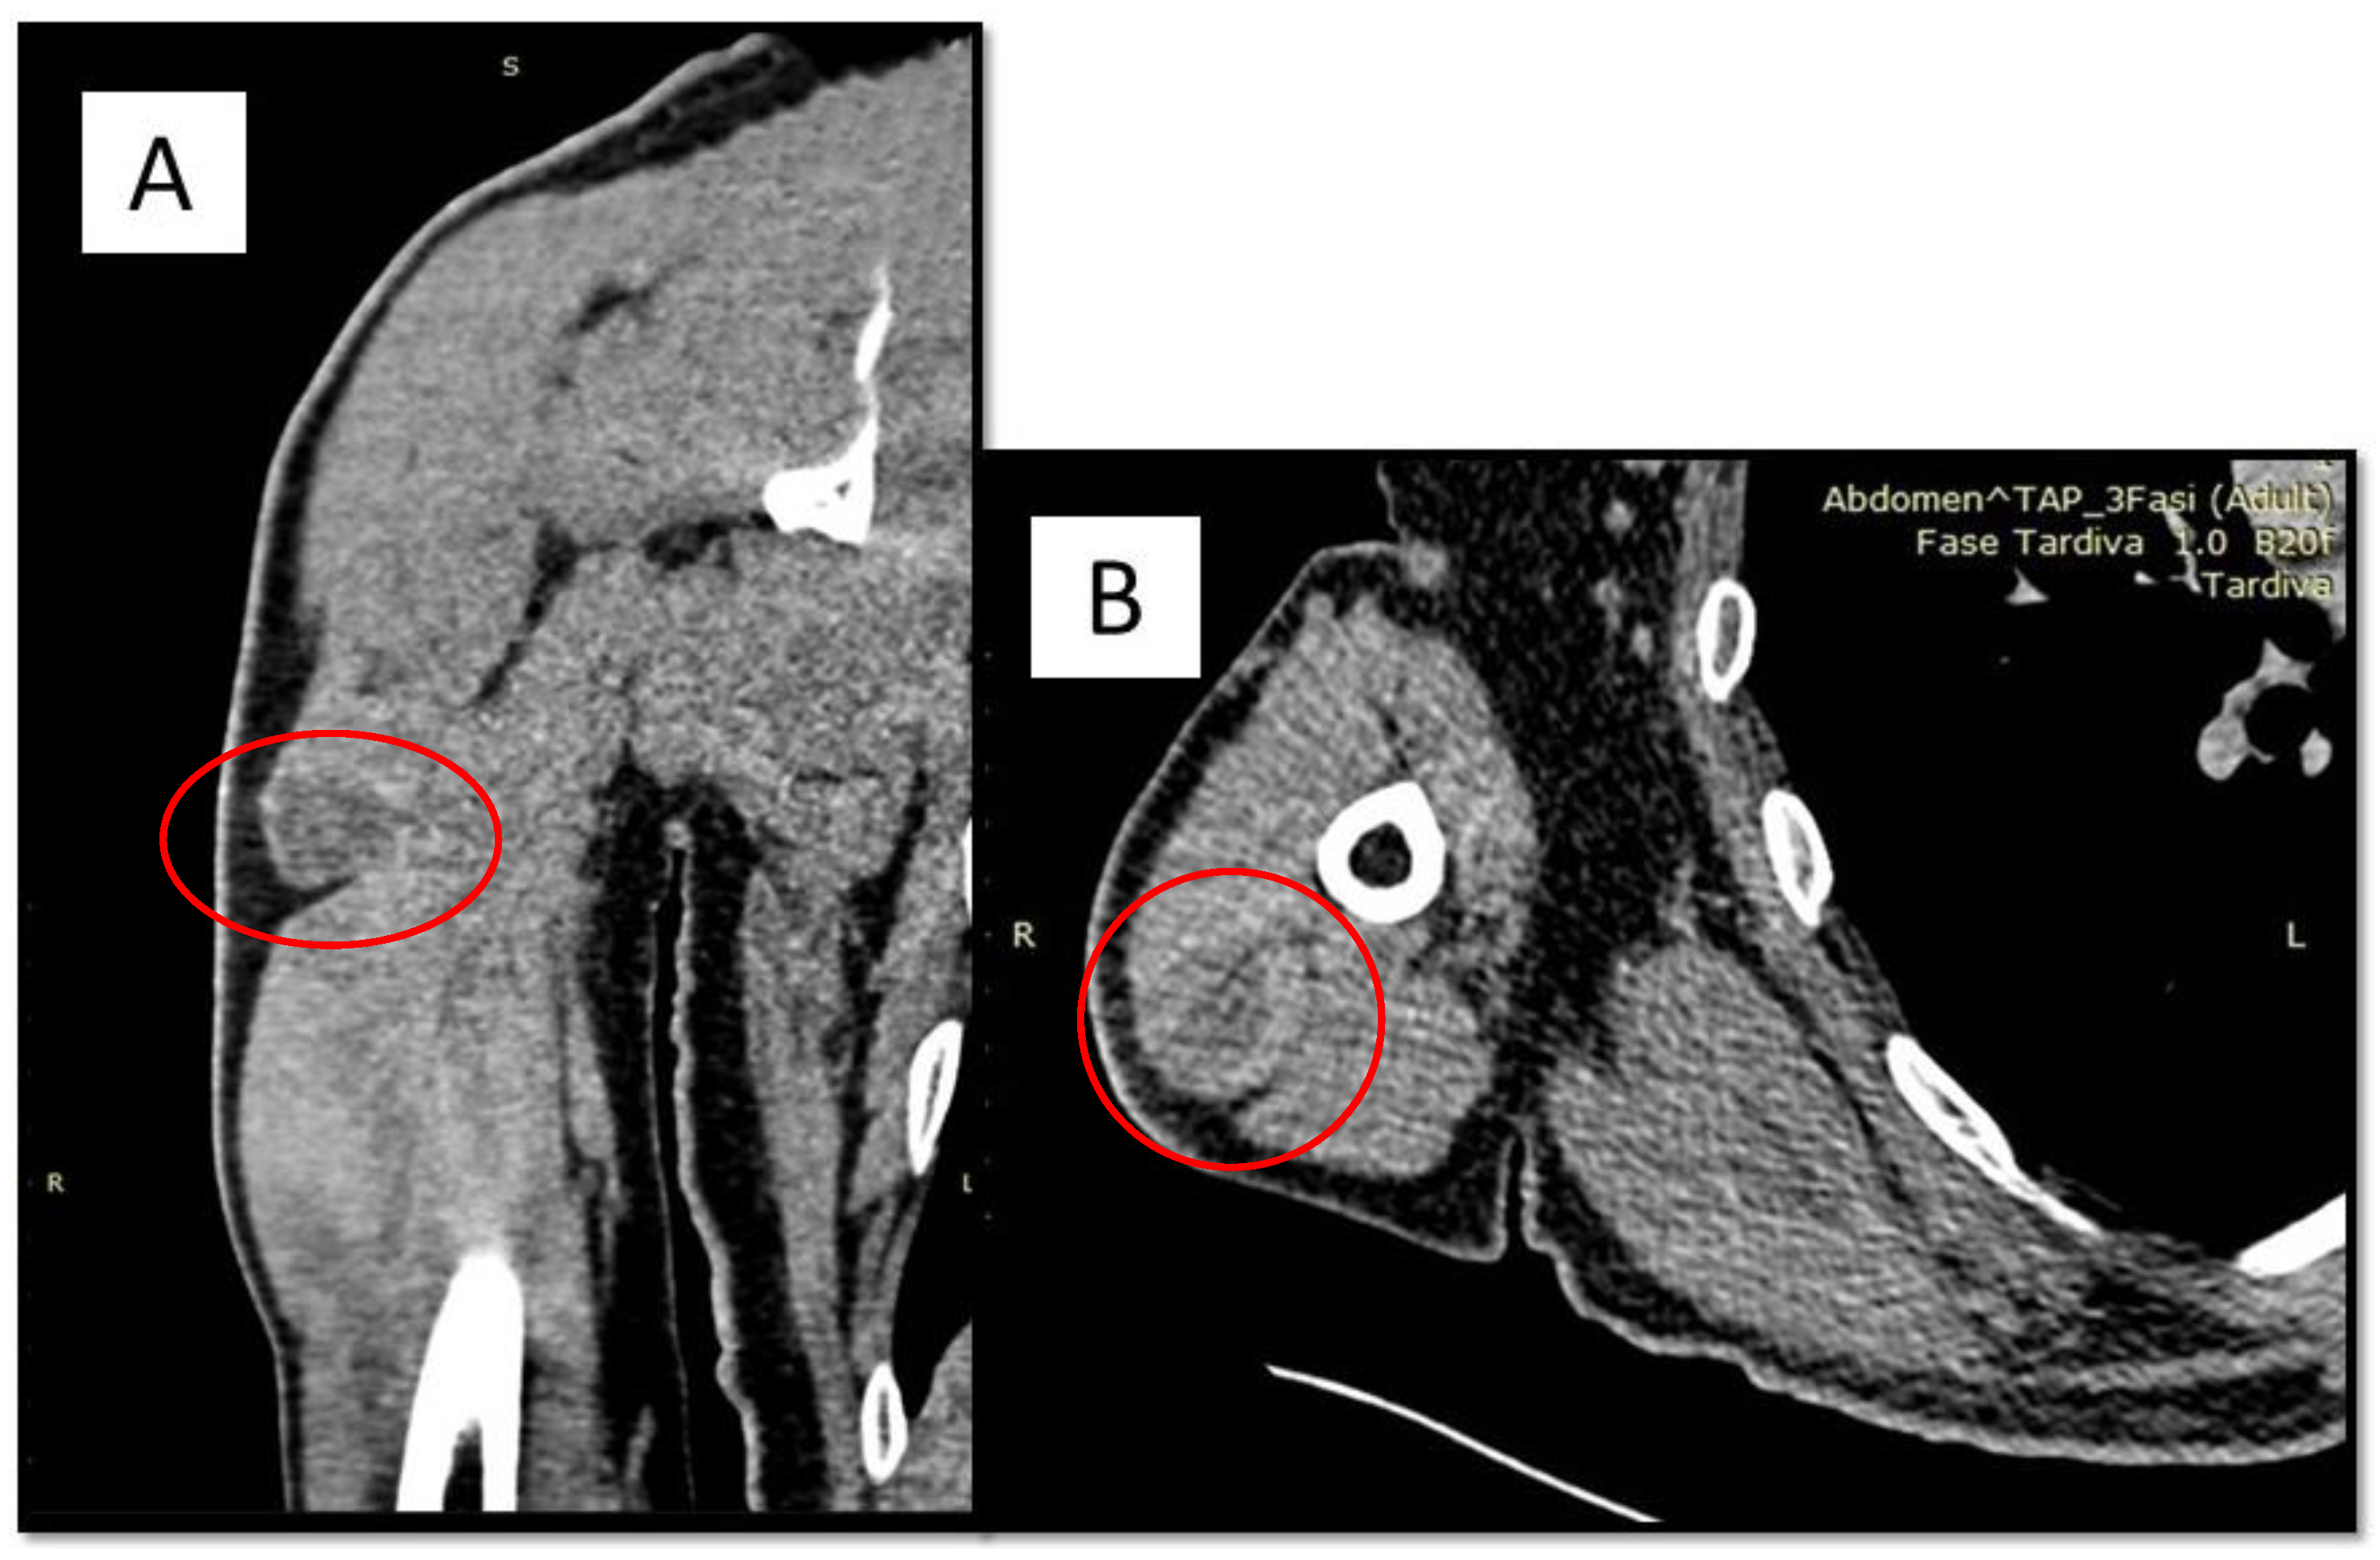

Angiomatoid Fibrous Histiocytoma (AFH) of the Right Arm: An Exceptional Case with Pulmonary Metastasis and Confirmatory EWSR1::CREB1 Translocation

Cazzato, G.; Lupo, C.; Casatta, N.; Riefoli, F.; Marzullo, A.; Colagrande, A.; Cascardi, E.; Trabucco, S.M.R.; Ingravallo, G.; Moretti, B.; et al. Angiomatoid Fibrous Histiocytoma (AFH) of the Right Arm: An Exceptional Case with Pulmonary Metastasis and Confirmatory EWSR1::CREB1 Translocation. Diagnostics 2022, 12, 2616. https://doi.org/10.3390/diagnostics12112616